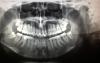

Feliz23 Опубликовано 15 апреля, 2013 Автор Поделиться Опубликовано 15 апреля, 2013 Добрый день! Снова вернулась сюда. Прошло 4 месяца с момента удаления зубов мудрости справа. с верхом всё ок, а вот низ меня беспокоит, а точнее нижняя правая 7-ка. Десна зажила, но по моим ощущением она стала ниже чем была, зуб немножко качается, реагирует иногда на холодное и когда я смыкаю зубы, то верхняя 7ка-его как бы задевает и я всё это чувствую, то есть полноценно сомкнуть я их не могу. И нижняя 7-ка стала выше на 1-2 мм по сравнению с соседними зубами в ряду, на снимке до удаления 7-ка стоит на ровне. Плюс ко всему когда я широко открываю рот и пытаюсь выдвинуть нижнюю челюсть вперёд, как если снимок делается, то слышу хруст в суставах с обеих сторон.Вопрос такой, что видно по снимку?(конкретно нижняя правая 7-ка- на снимке она слева).могут ли мои ощущения быть из за скученности зубов впереди? Ссылка на комментарий

Премоляр Опубликовано 16 апреля, 2013 Поделиться Опубликовано 16 апреля, 2013 Есть снимок до удаления?Разумеется,7 немного сместилась дистально и вертикально,т.к. убрали давление на нее сзади. Естественно,он немного подвижен и десна за ним опущена,т.к. там была 8 ка.Суставная симптоматика может быть из-за широкого откр,рта во время удаления,что обычно проходит спустя неделю. Может быть и из-за незначительного вертикального выдвижения 7 ки. Невозможно определиться с планом,видя ТОЛЬКО один снимок. Написал приблизительн...Обратитесь на повторный осмотр к хирургу. Если все ок,он направит вас к ортодонту для дальнейшего наблюдения/диагностики. Ссылка на комментарий

Feliz23 Опубликовано 19 апреля, 2013 Автор Поделиться Опубликовано 19 апреля, 2013 Вот снимок до удаления восьмерок! Сделан в сентябре 2011 года! Ссылка на комментарий

Премоляр Опубликовано 20 апреля, 2013 Поделиться Опубликовано 20 апреля, 2013 (изменено) http://i053.radikal.ru/1304/c0/d4be337ff221.jpg http://s017.radikal.ru/i443/1304/02/439dcb12678b.jpg Нарисовал приблизительно. ОПТГ-это не показатель,часты искажения отображения зубов. Я уже писал,что вам необходимо проконсультироваться с ортодонтом для диф.диагностики и возможного планирования дальнейших действий. Без окклюзионных фото и дополнительных диагностич.манипуляций невозможно выявить точную причину. Так просто гадаем... Изменено 20 апреля, 2013 пользователем Премоляр Ссылка на комментарий